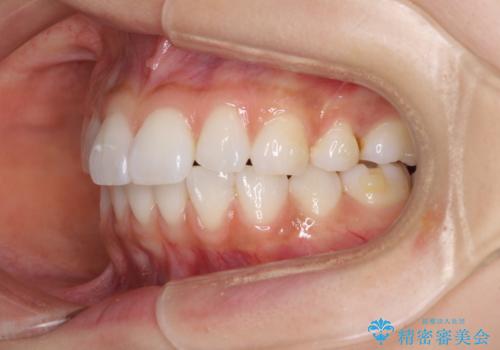

矯正治療の後戻り インビザラインによる再矯正治療

- 以前ワイヤー装置にて行った抜歯矯正の後戻りを気にして来院された患者様です。

前歯のデコボコにより、やや口元が突出した印象となっていたため、口元も引っ込めることとしました。

上下顎前歯に積極的にIPR(歯と歯の間を削る)を行い、インビザラインを用いて治療していくこととしました。

デコボコが解消されるのはもちろんのこと、突出感のあった前歯を引っ込めることができ、患者様には大変満足していただきました。